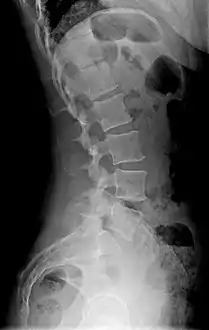

X-ray of lumbar hyperlordosis

Measurement and diagnosis of lumbar hyperlordosis can be difficult. Obliteration of vertebral end-plate landmarks by interbody fusion may make the traditional measurement of segmental lumbar lordosis more difficult. Because the L4–L5 and L5–S1 levels are most commonly involved in fusion procedures, or arthrodesis, and contribute to normal lumbar lordosis, it is helpful to identify a reproducible and accurate means of measuring segmental lordosis at these levels.[16][17] A visible sign of hyperlordosis is an abnormally large arch of the lower back and the person appears to be puffing out his or her stomach and buttocks.

Precise diagnosis is done by looking at a complete medical history, physical examination and other tests of the patient. X-rays are used to measure the lumbar curvature. On a lateral X-ray, a normal range of the lordotic curvature of between 20° and 60° has been proposed by Stagnara et al., as measured from the inferior endplate of T12 to the inferior endplate of L5.[18] The Scoliosis Research Society has proposed a range of 40° and 60° as measured between the upper endplate of Th12 and the upper endplate of S1.[18] Individual studies, although using other reference points, have found normal ranges up to approximately 85°.[18] It is generally more pronounced in females.[18] It is relatively constant through adolescence and young adulthood, but decreases in the elderly.[18]